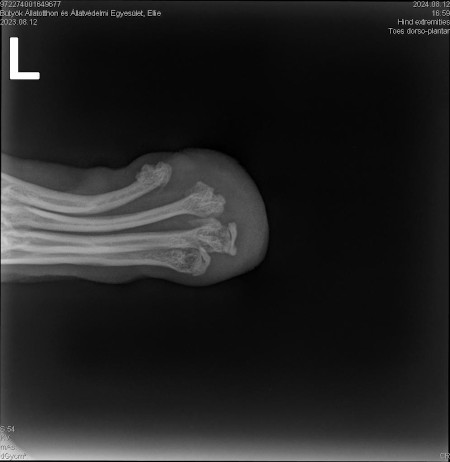

| Bemerkungen | Ellie fehlt am linken Hinterbein der Fuss/die Pfote |

Ellie ist ca. 1 Jahr alt (Stand 08/2024) und hat bereits eine bewegte Vergangenheit hinter sich. Nach 5 Tagen intensiver Versuche konnte sie endlich von der Strasse gerettet werden, wo sie hungrig, durstig und in einem schlechten gesundheitlichen Zustand allein und orientierungslos umherirrte. Elli war von Flöhen und Zecken geplagt und stark abgemagert, doch trotz all dieser Herausforderungen zeigt sie einen unglaublichen Lebenswillen. Elli hat ein Handicap: Ihr fehlt ein Fuß am Hinterbein. Ob dies auf einen Unfall oder eine angeborene Fehlbildung zurückzuführen ist, wissen wir nicht. Doch Elli lässt sich davon nicht einschränken! Sie zeigt sich flink und steckt voller Energie. Ellie kommt erstaunlich gut mit ihrem Bein zurecht, es stört sie in keiner Weise und sie kann problemlos laufen, spielen und sogar rennen. Dennoch benötigt sie einen Schutz für ihren Stummel, entweder eine passende Prothese oder einen gefütterten Silikonschuh. Dies sollte in ihrem neuen Zuhause gründlich tierärztlich abgeklärt werden. Trotz ihrer Vergangenheit ist Elli eine unglaublich liebe, verschmuste und fröhliche Hündin. Sie liebt die Nähe zu Menschen, ist sehr anhänglich und versteht sich gut mit anderen Hunden. Ihre neuen Menschen sollten Freude daran haben, ihr alles ruhig und geduldig beizubringen, was so ein junges Mädel für ihr weiteres Leben als Familienhündin wissen muss. Ebenso sollten sich die neuen Besitzer bewusst sein, dass ein Hund nicht nur Freude, sondern auch jede Menge Arbeit und Verantwortung mit sich bringt, damit Ellie sich zu einer tollen Begleiterin entwickeln kann. Für unsere Herzensbrecherin suchen wir ein liebevolles, fürsorgliches und dauerhaftes Zuhause, wo sie nebst viel Spass auch abwechslungsreiche Spaziergänge erleben darf, wo sie artgerecht ausgelastet wird und täglich die Zuwendung und Pflege bekommt die sie verdient. Wer erfüllt den Traum von unserer Zuckerschnute Ellie und gibt ihr trotz ihres kleinen Handicaps die Chance ein treues Familienmitglied zu werden?